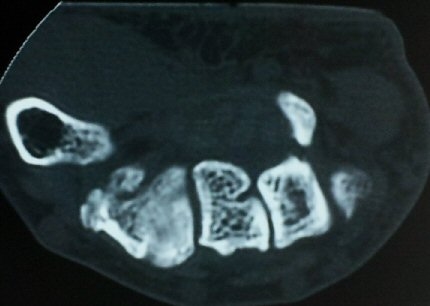

ÀÚ±â°ø¸í°Ë»ç

ÄÄÇ»ÅÍ ÃÔ¿µ»ó °¥°í¸®»À °¥°í¸® °ñÀýÀ» º¸ÀÓ(±×¸² 5, 6, 7).